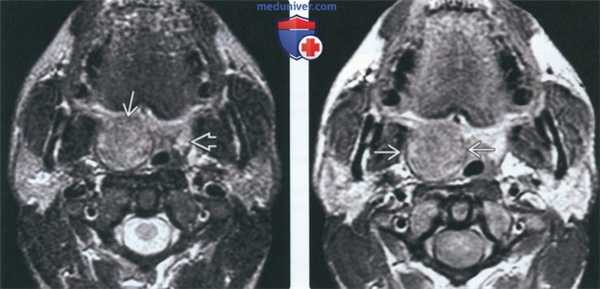

(Слева) МРТ Т1ВИ, аксиальная проекция. Медиальнее от правой внутренней сонной артерии располагается мягкотканное образование, представляющее собой увеличенный заглоточный лимфоузел. Обратите внимание, что, несмотря на свои размеры, лимфоузел никак не деформирует контуры глотки, поэтому при осмотре увидеть его невозможно. В прошлом пациент перенес апластическую анемию и трансплантацию костного мозга.

(Справа) МРТ Т1ВИ с КУ, коронарная проекция, этот же пациент. Вокруг лимфоузла отмечается кольцо накопления контраста, внутри него - зона некроза. У пациента диагностирована посттрансплантационная неходжкинская лимфома.

3. МРТ при неходжкинской лимфоме заглоточных лимфоузлов:

• Т1ВИ:

о Сигнал от лимфоузлов изоинтенсивен сигналу от мышечной ткани

• Т2ВИ:

о Гиперинтенсивный сигнал

• STIR:

• Т1ВИ с КУ:

о Диффузное незначительное или умеренное накопление контраста